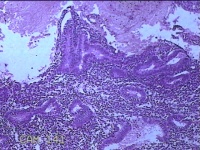

子宫腔内膜组织

性别

女

年龄

44岁

临床诊断

子宫异常出血、甲亢、轻度贫血

一般病史

阴道流血20天,加重1天。

标本名称

大体所见

灰白暗红色不规则碎组织3x2.8x0.3cm一堆。

图1

貌似增生反应子宫内膜。